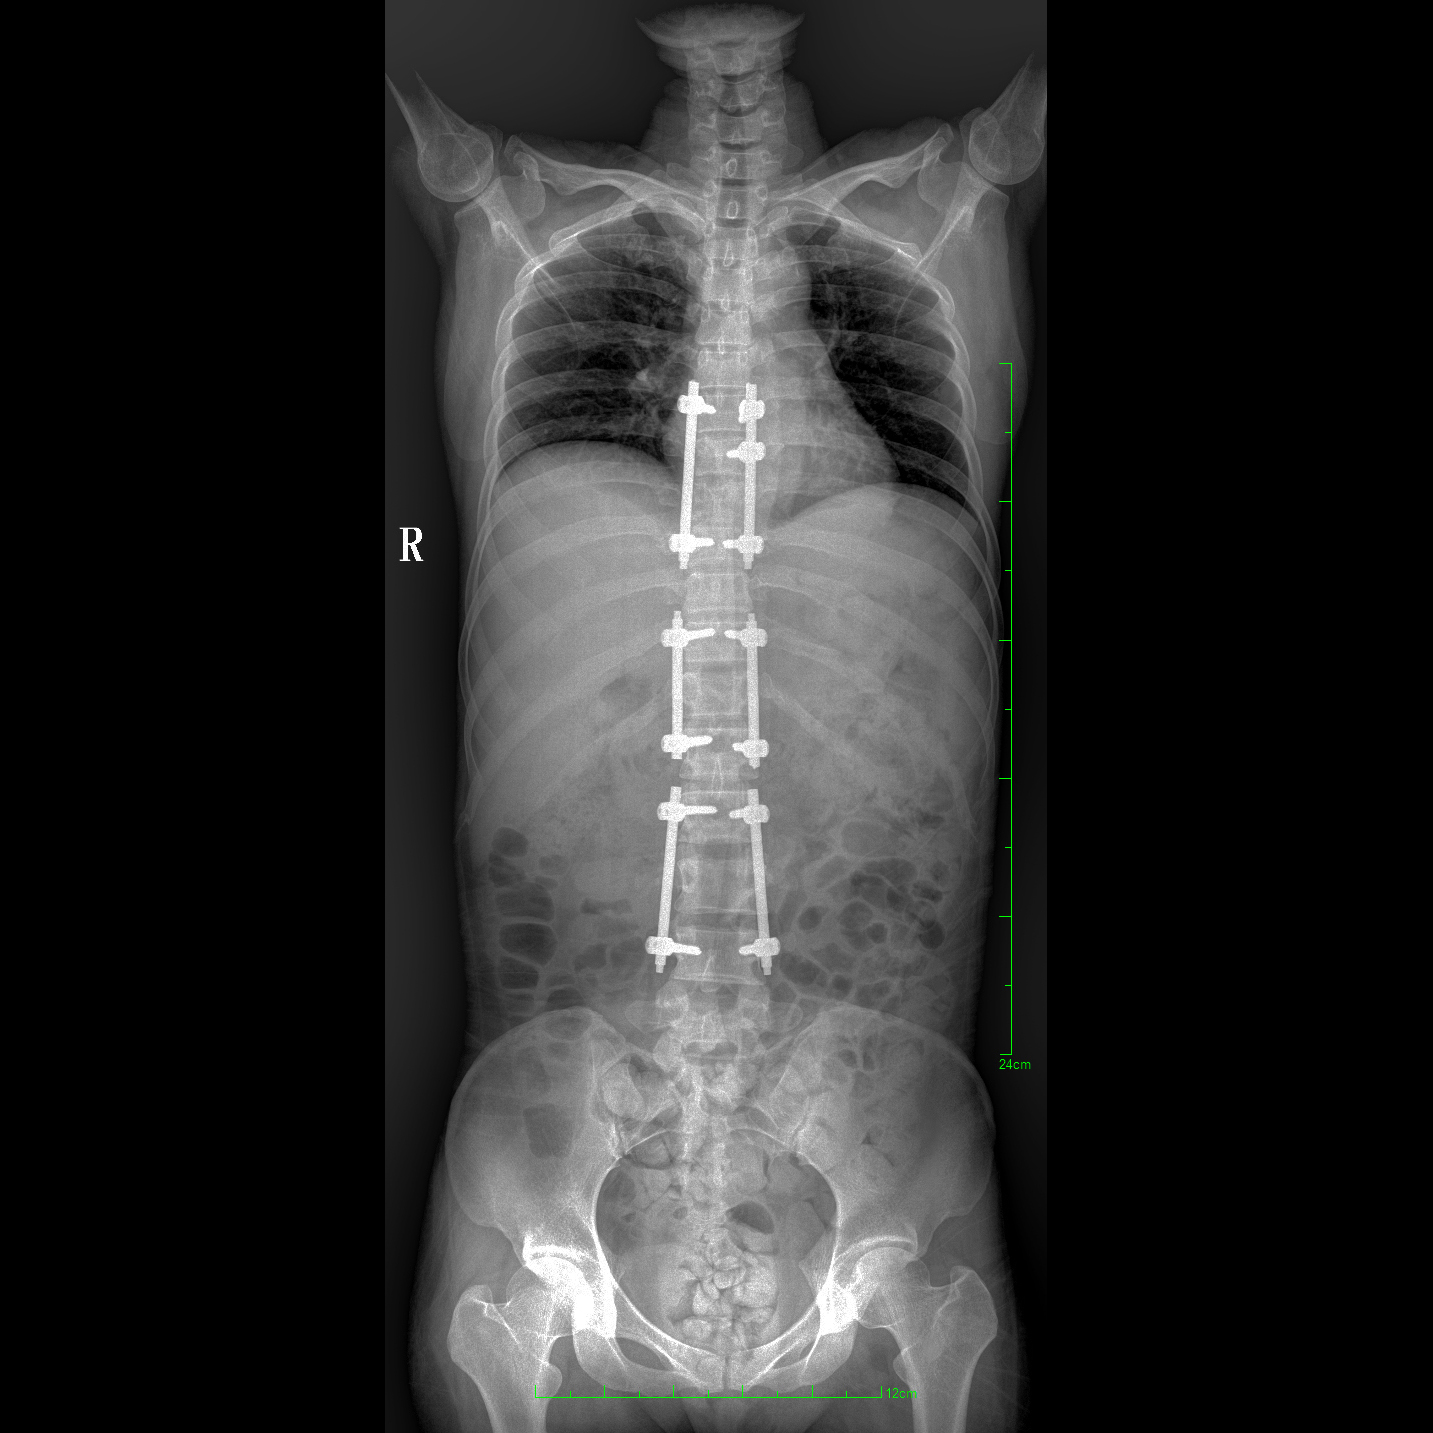

支持全脊柱攝影、雙下肢攝影、脊髓造影、復(fù)雜創(chuàng)傷、人工關(guān)節(jié)置換、關(guān)節(jié)損傷的修復(fù)重建等大視野臨床應(yīng)用

17"*34"有效視野,一次成像不拼接。相較于多張攝影再軟件拼接的DR設(shè)備,PLX8600解決了拼接圖像存在密度不均勻,拼接處圖像配準(zhǔn)和放大效應(yīng)等問(wèn)題,給臨床帶來(lái)了大視野影像解決方案,可一次性覆蓋全脊柱或雙下肢影像。